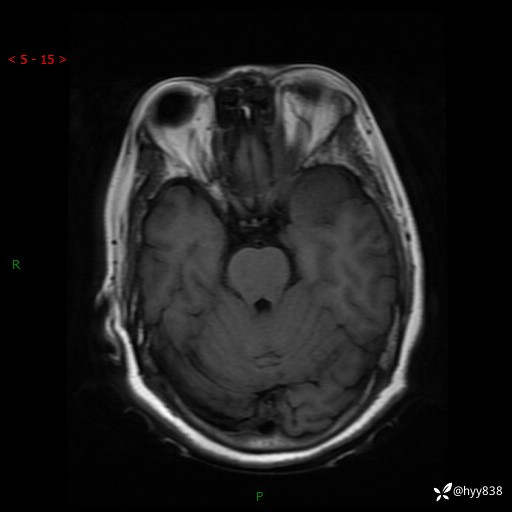

现病史:患者于1个月前无明显诱因出现左眼视力下降,无头痛,无恶心、呕吐,无肢体活动障碍,无意识障碍等伴随症状,后就诊于监利市人民医院行眼眶MRI检查提示“左侧中颅窝底占位性病变”,今日为求进一步诊治前来我院,门诊以“颅内占位性病变”收入院。 发病以来,患者精神、饮食及睡眠良好,大、小便正常。

颅脑MRI平扫+增强